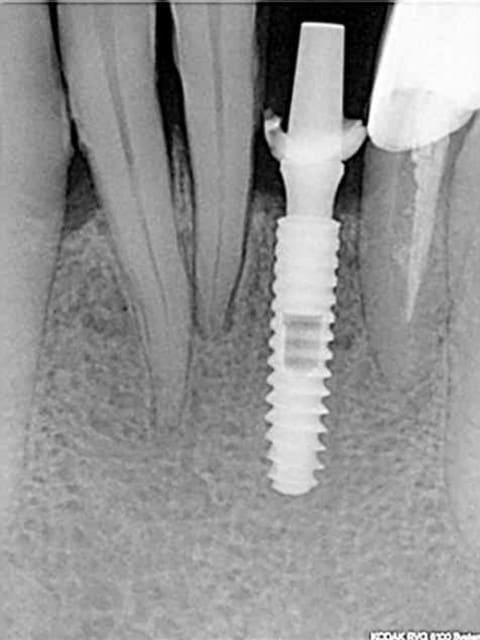

Je l'ai utilisé il y a 5 ans sur une canine en potection totale (Pas le choix car en classe 2- 2).Depuis c'est la PM derrière qui a laché. Je te joins la RX.

--

Rx implant cad 2 cpyqbp - Eugenol

rx à j=0 et j+4 mois

ce qui est surprenant , c'est la présence d'os au niveau du col.